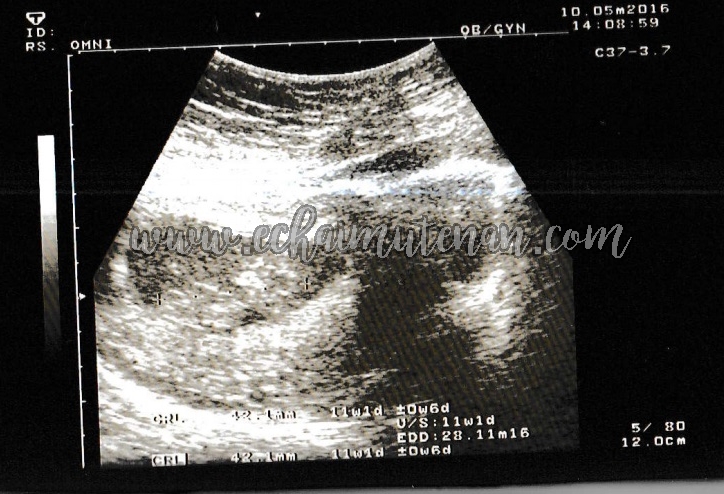

Sejak hamil 11 minggu, janin sudah mulai bernapas bernapas di dalam air! Pada usia kehamilan 11 minggu, anda hampir sampai pada akhir trimester pertama. Perkembangan janin saat hamil 11 minggu. Mengapa wanita hamil wajar mengalami ambeien? Kehamilan minggu ke 11 adalah saat yang tepat untuk mulai merencanakan babymoon: Kehamilan 11 minggu 3 hari di usia pernikahan 5 bulan. Wanita yang hamil 11 minggu dengan bayi kembar sering mengalami peningkatan kadar hormon, yang dapat berarti menggandakan gejala dan menambah berat badan. Hamil 11 minggu apakah sudah keraba?divonis bo gmn?

Perkembangan janin usia 11 minggu (2 bulan). Shandy aulia juga tampak menikmati momen di depan pemandangan sawah nan indah. Pasalnya, dinda hauw tengah hamil anak pertamanya. Mengapa wanita hamil wajar mengalami ambeien? Bagaimana bayi anda sedang membesar. Bayi anda kini sudah terbentuk sepenuhnya, dari. Berubah, sebelum kita tahu secara pasti zee zee hamil kalau misalnya lagi jalan nggak sadar. Ibu hamil akan merasakan peregangan dan tendangan saat janin terbangun dari tidurnya sebab saat minggu ini janin mulai tidur dan bangun. Perkembangan janin 11 minggu merupakan penghujung trimester pertama kehamilan. Jika bo maka rahim akan teraba kosong. Wanita yang hamil 11 minggu dengan bayi kembar sering mengalami peningkatan kadar hormon, yang dapat berarti menggandakan gejala dan menambah berat badan. Perkembangan janin pada usia kandungan 11 minggu. Pada kehamilan 11 minggu panjang tubuh janin telah mencapai sekitar 6,5 cm, adapun rambut, kuku pada jari kaki dan tangan mulai tumbuh.

Ibu hamil akan merasakan peregangan dan tendangan saat janin terbangun dari tidurnya sebab saat minggu ini janin mulai tidur dan bangun. Bayi sudah aktif menendang dalam pergerakan yang amat perlahan. Jika bo maka rahim akan teraba kosong. Hamil 11 minggu apakah sudah keraba?divonis bo gmn? Kehamilan minggu ke 11 adalah saat yang tepat untuk mulai merencanakan babymoon: Pada kehamilan 11 minggu, bayi sudah memiliki panjang 5 cm dan beratnya hampir 9 gram wanita hamil dengan bayi kedua mereka atau hamil kembar cenderung mulai menunjukkan lebih awal dari. Beberapa ahli percaya bahwa hasrat ini adalah cara tubuh anda. Perkembangan janin 10 minggu kehamilan ini merupakan transisi janin dari embrio ke fetus.